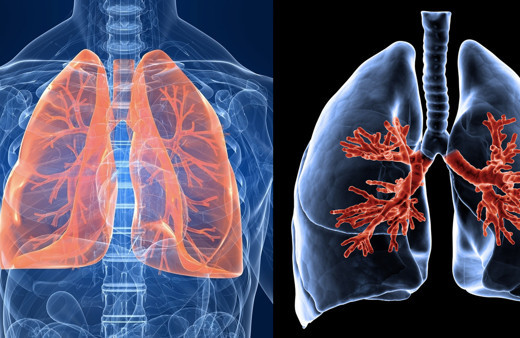

Akciğer